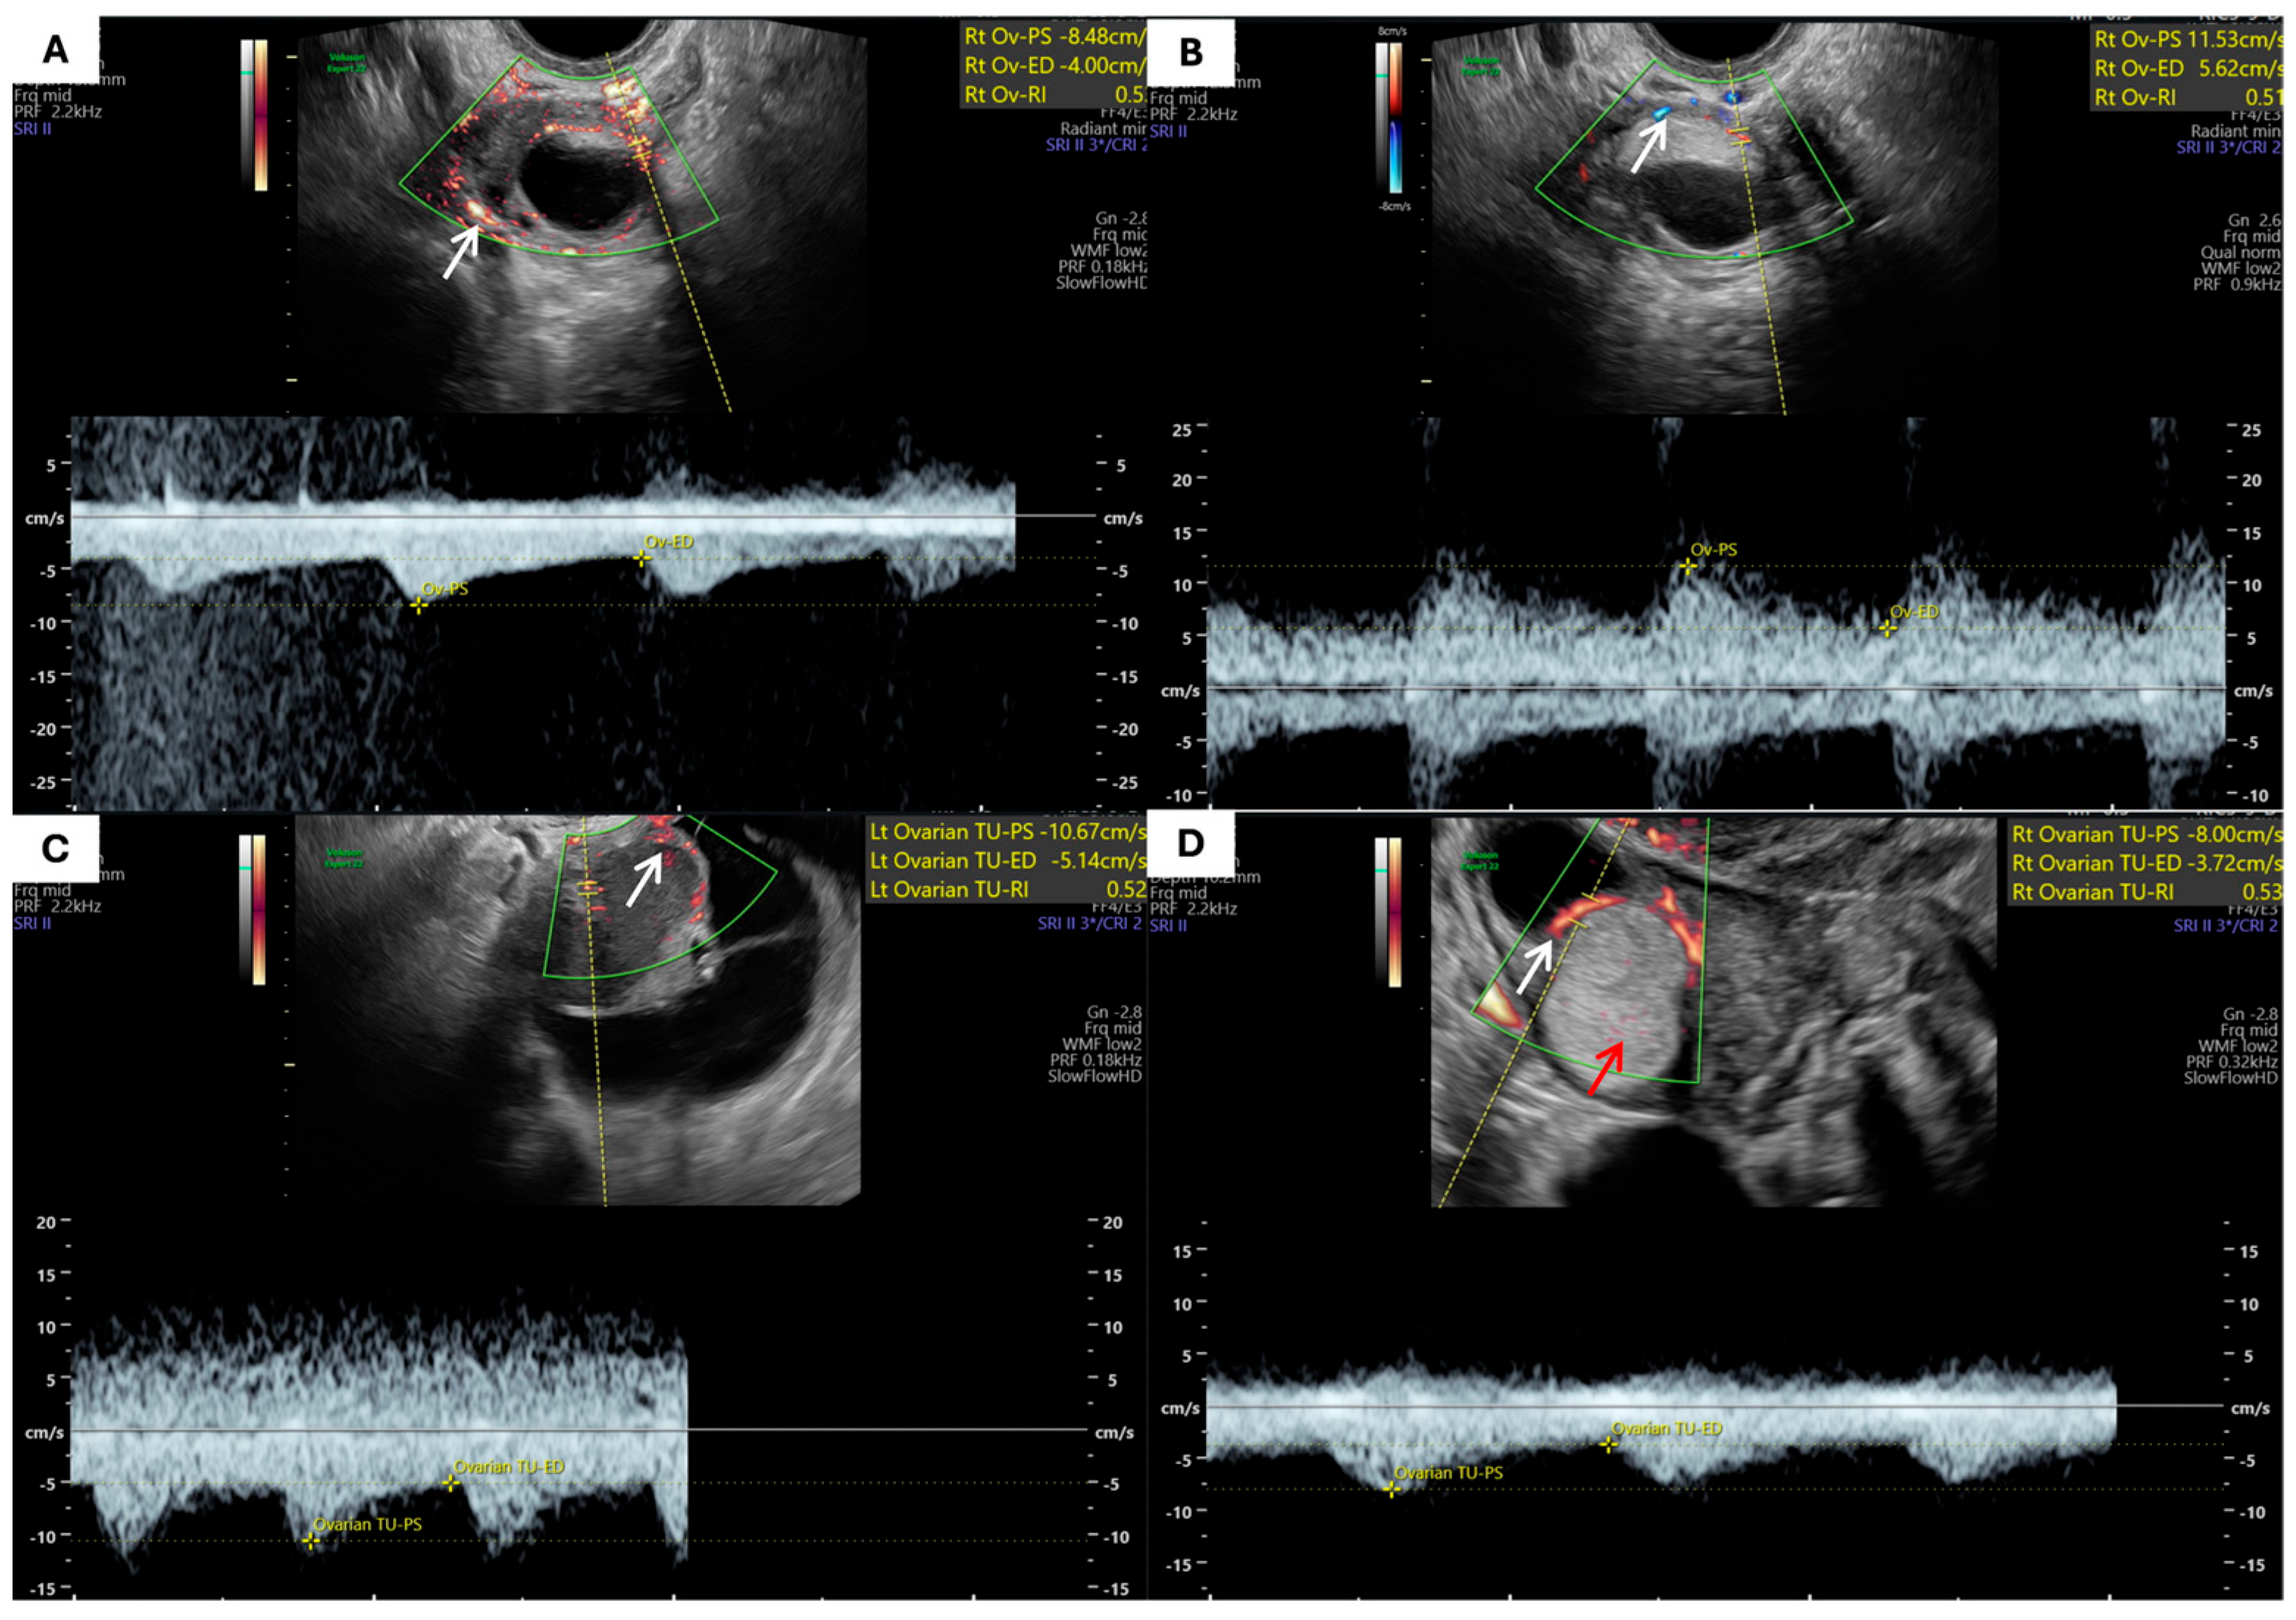

- Hemodynamic Parameters: Assessed using color and pulsed Doppler techniques. The location of blood flow (pericystic, intracystic, in septa) was noted. The peak systolic velocity (Vmax), end-diastolic velocity (Vmin), and Resistance Index (RI) were measured from spectral Doppler waveforms. Measurements were also taken from the ipsilateral uterine artery to obtain its Resistance Index (AURI).

| Parameter | Endometriomas | MCTs | p-Value |

|---|---|---|---|

| Total number of analyzed blood vessels (across all tumors) | 168 | 149 | — |

| Mean number of blood vessels (n ± SD) | 3.03 ± 1.67 | 3.00 ± 2.30 | 0.5 |

| Localization of blood vessels (n) | 0.5 | ||

| – Pericystic | 125 | 111 | |

| – In septa | 24 | 20 | |

| – Within the papillary projection | 6 | 2 | |

| – Within the solid-appearing components * | 13 | 16 |

| Parameter (n ± SD) | Endometriomas | Ovarian Teratomas | p-Value |

| RI | 0.57 ± 0.11 | 0.54 ± 0.13 | 0.04 * |

| Vmax | 10.72 ± 5.56 | 10.28 ± 5.96 | 0.5 |

| Vmin | 4.43 ± 2.24 | 4.34 ± 2.20 | 0.7 |

| AURI tumor | 0.81 ± 0.14 | 0.83 ± 0.07 | 0.02 * |

| AURI contralateral | 0.84 ± 0.07 | 0.85 ± 0.07 | 0.7 |

| ΔAURI | 0.03 ± 0.11 | 0.01 ± 0.07 | 0.8 |

| AUVmax tumor | 42.62 ± 21.73 | 38.10 ± 15.0 | 0.2 |

| AUVmax contralateral | 36.80 ± 17.27 | 34.50 ± 13.45 | 0.5 |

| ΔVmaxAU | 4.73 ± 24.28 | 3.23 ± 14.88 | 0.6 |